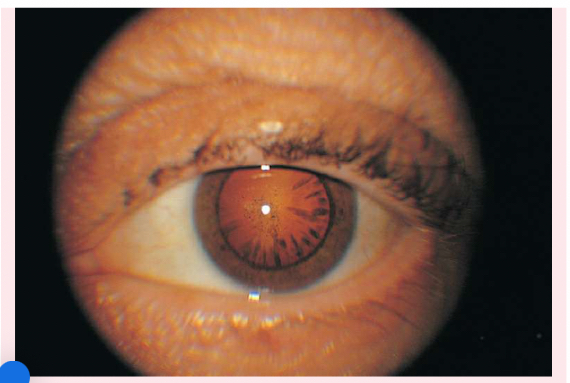

Peripheral cataracts

look like gray spokes that point inward when seen with a flashlight; they look like black spokes that point inward against the red reflex when seen through an ophthalmoscope.